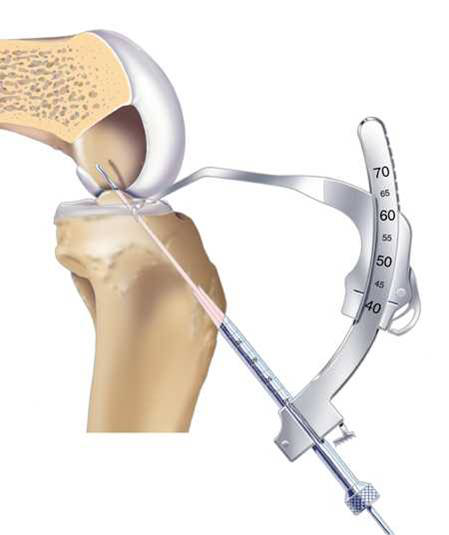

Rigidfix-Intrafix 固定。Rigidfix為PLLA可吸收螺釘。Intrafix是將擠壓釘置于釘鞘內(nèi),防止螺釘對(duì)移植物的直接損傷,同時(shí)達(dá)到360度固定,其材料為CP/PLA,具有誘導(dǎo)成骨和可吸收性

Rigidfix固定

Intrafix固定